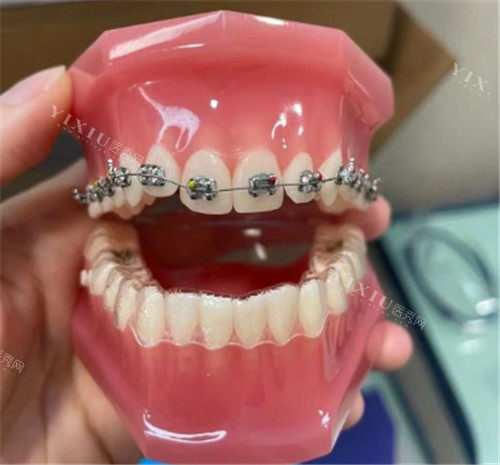

金属矫正是一种传统且应用广泛的矫正方式。它通过在牙齿表面粘接金属托槽,并利用弓丝施加力量来移动牙齿,从而改善牙齿排列不齐等问题。金属矫正的适用范围广,可以应用于各种错颌畸形的矫治,包括牙齿排列不齐、牙齿突出、牙齿拥挤、牙齿稀疏等。它的结果稳定,能够提供持续且稳定的矫治力,有利于牙齿的移动和排列。而且,金属矫正的可调整性强,医生可以通过调整弓丝的力量和位置,精细调整矫治结果,以达到更好的矫治目的。

金属矫正的优点在于价格相对较低,对于大多数患者来说经济负担较小。然而,它的美观性较差,金属托槽在牙齿上的粘接可能会影响美观,特别是在微笑时容易暴露。同时,舒适度也较差,金属托槽和弓丝可能会对口腔黏膜造成刺激,导致口腔溃疡、牙龈炎等问题,且不易清洁,容易残留食物残渣和细菌,增加龋齿和牙周疾病的风险。此外,金属矫正需要定期复诊,复诊频率较高,可能会影响患者的日常生活和工作。